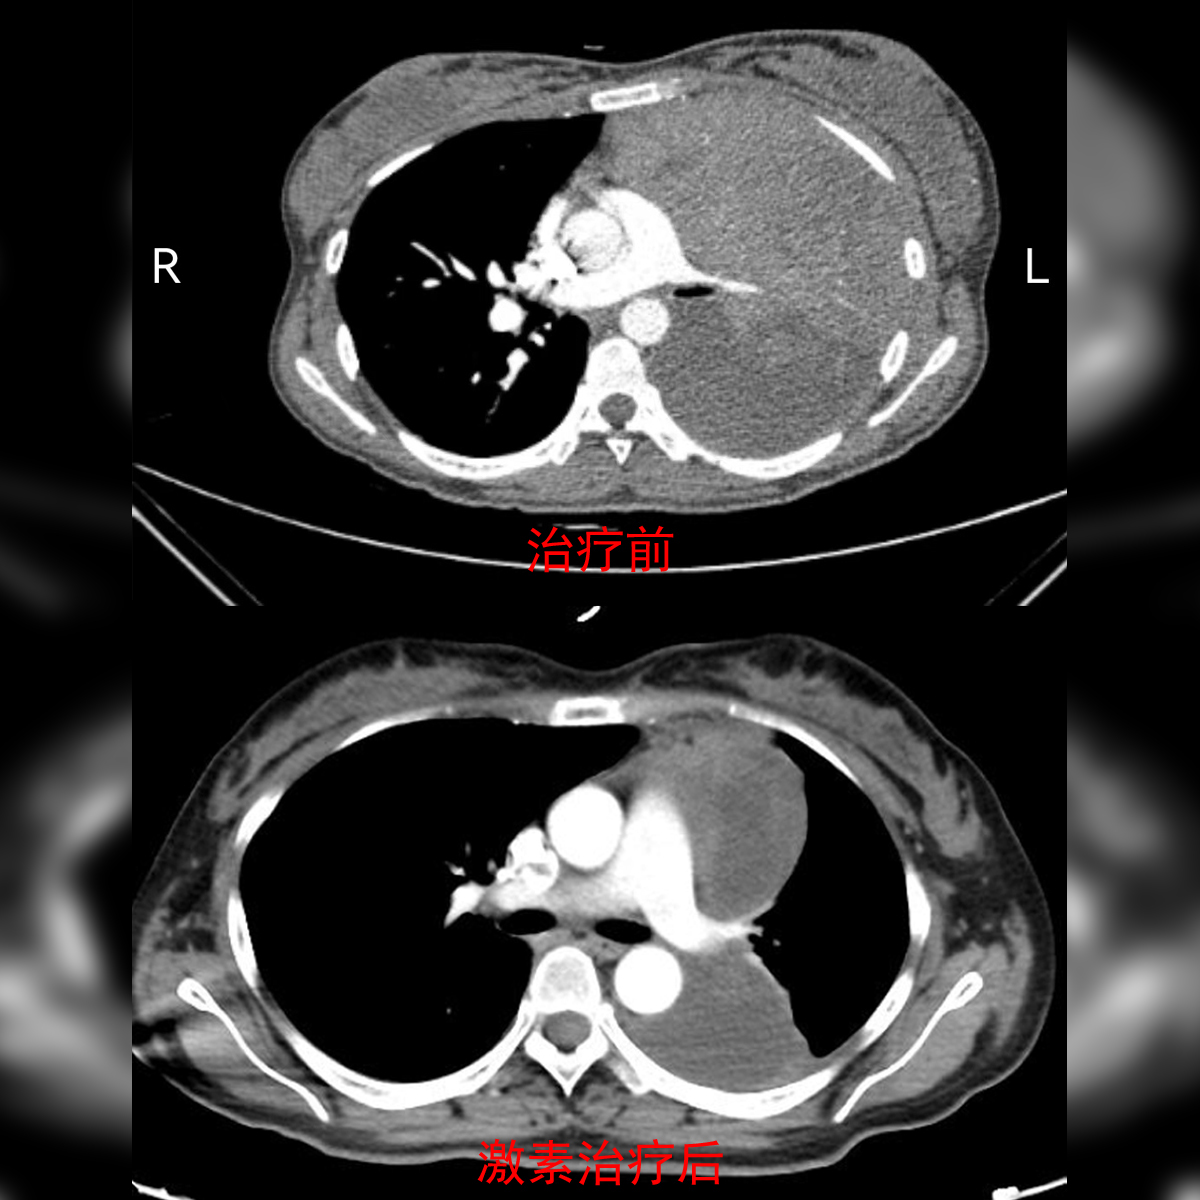

治疗前和激素治疗后的影像学对比图。

按照医嘱服药一段时间后,胡女士的肿块明显缩小了。通过便捷的互联网医院系统,方文涛明确了她的病情,告诉他们“可以过来手术了。”那时,胡女士体内的肿块虽然已消减,但仍然是个直径近20公分的“大家伙”,而且侵犯周围血管、神经和左肺,还长进了心脏外面的包膜内,手术风险非常高。术中,如果损伤到喉返神经,会导致患者出现声音嘶哑等症状。更让人担心的是,她的胸膜上同时显示存在一个病灶,但并不知道是否为肿瘤转移。为应对各类情况,医生们制定了手术方案与应急预案。